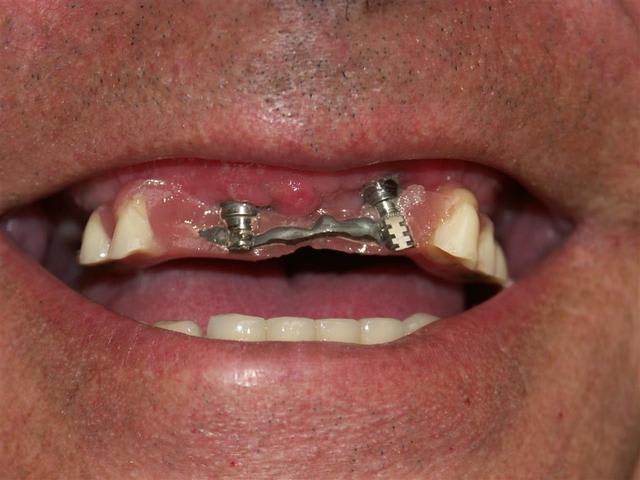

J'ai abandonné la MCI au maxillaire sur 4 implants c'est trop risqué.

Aucun filet de secours, je préfère avoir au moins 6 implants bloqués à min 30 Ncm, pour mettre en charge un maxillaire complet.

A la mandibule 4 implants, ça fonctionne très bien, j'en ai fait beaucoup aussi.

Voici déjà un cas avec 6 implants maxillaire et mandibulaire.

Le bas est pour le moment en résine, on doit passer plus tard à un bridge vissé sur armature métallique.